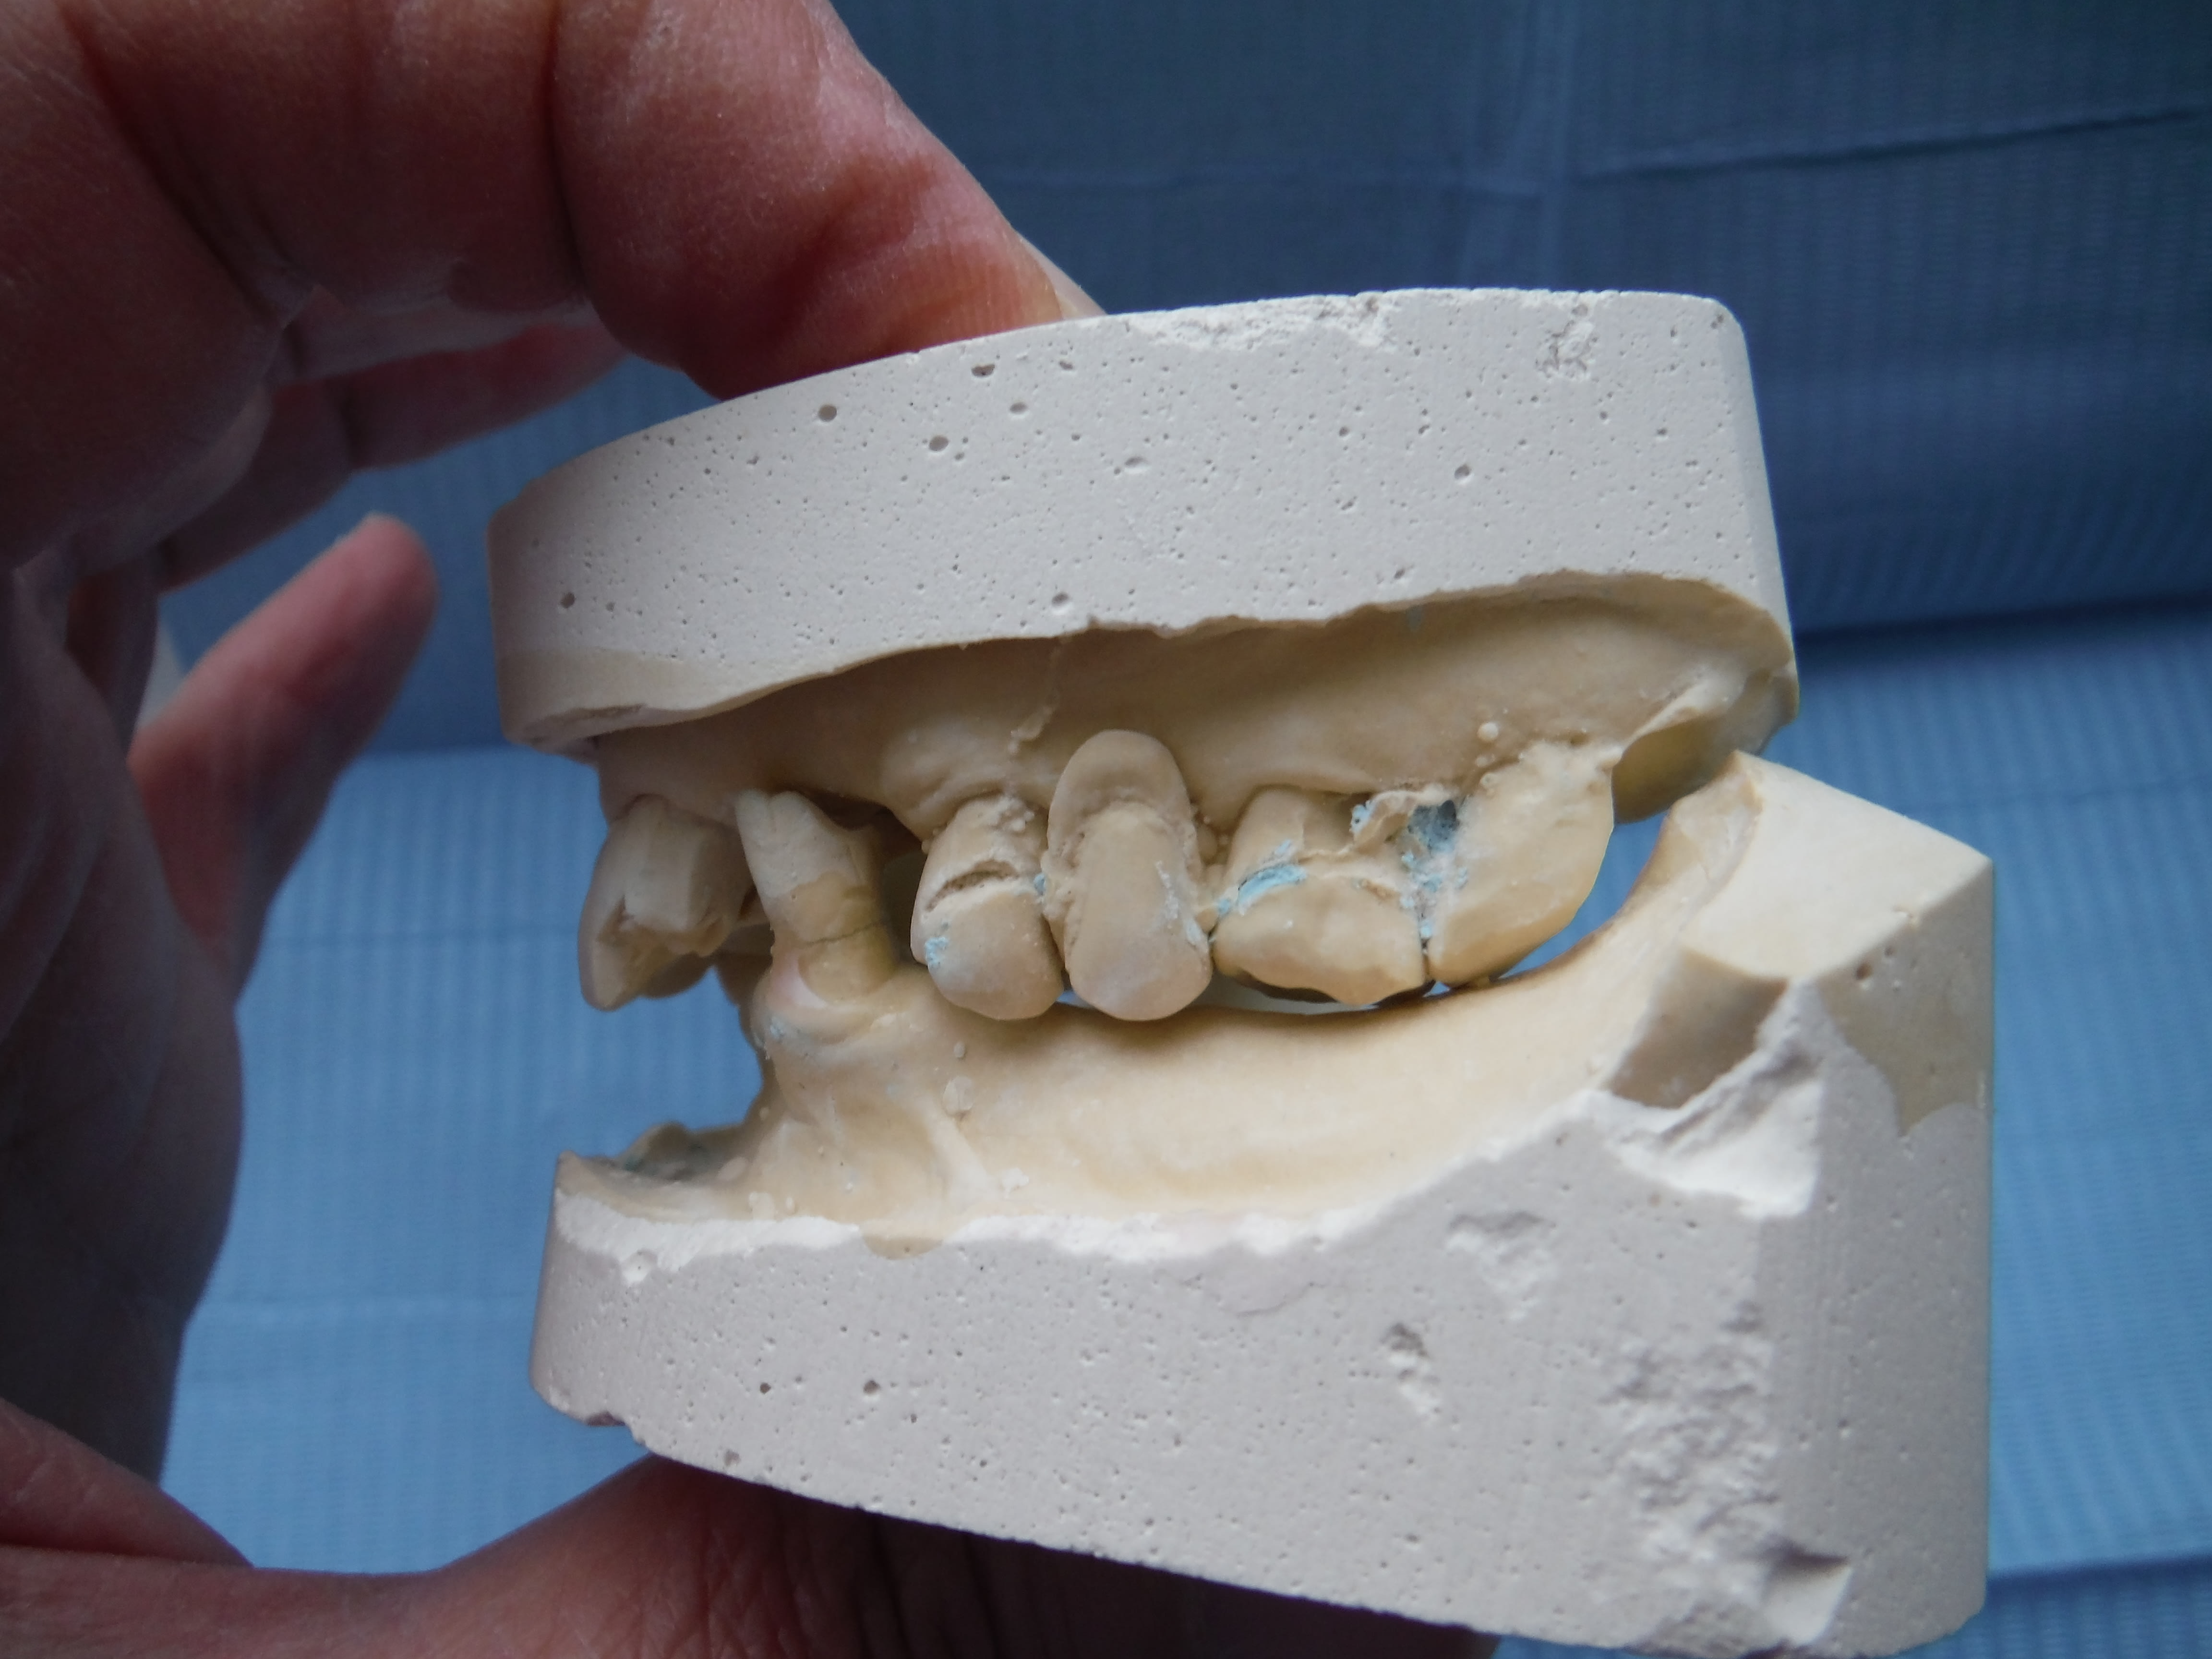

Et là tu vois quoi? Faut que j’adresse à un esssspécialiste?

Plus de 10 ans qu'il n'y a rien en bas, et là le coup de bol, elle s'est faite renverser par une voiture, avec les sous touchés elle va pouvoir se payer une pap/pac(?) C'est-y pas chouette?

La RC j't'en parle pas... trop simple!

Avec sa classe 3 squelettique , sa canine va taper pile poile sur le bord libre de la couronne sur Implant si je pose un implant !

ç est sur , elle va avoir une drôle de tronche la 12 , là on en est à boucher 1 trou , pas à faire du ouane eugaine staille .

ç est là qu'il serait bonard d'avoir la photo de sa parafonction nocturne en bout à bout canin .

pour la 12 ,faudrait lui faire un bout à bout quand elle est dans cette position de parafonction .

pour l'animer tu peux la mettre de traviol dans l'axe 37 /13 .